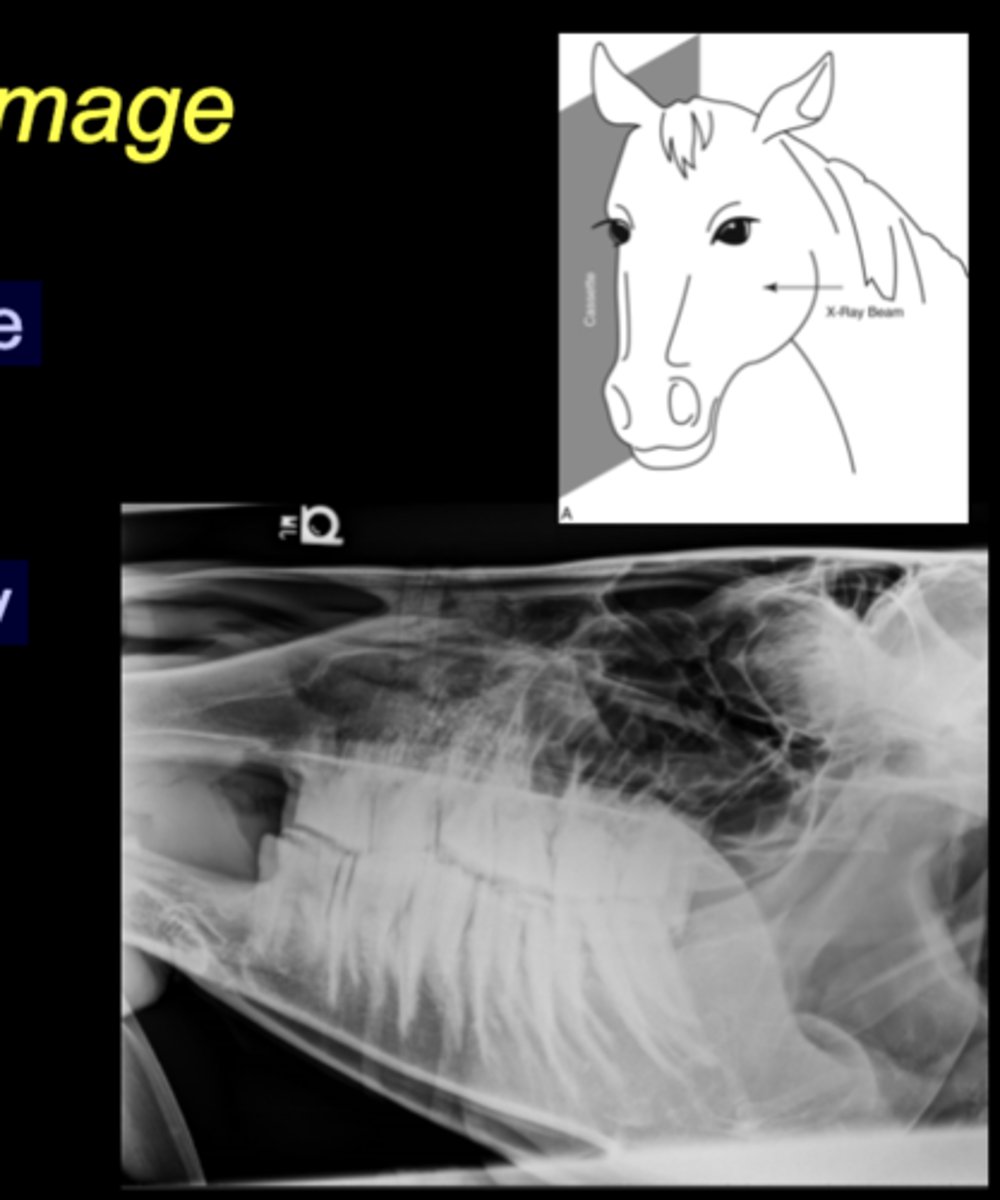

LG Animal Skull - Lateral image

• Tube on one side, plate on the other

• Marker to indicate laterality closest to plate

Equine Spine Lateral